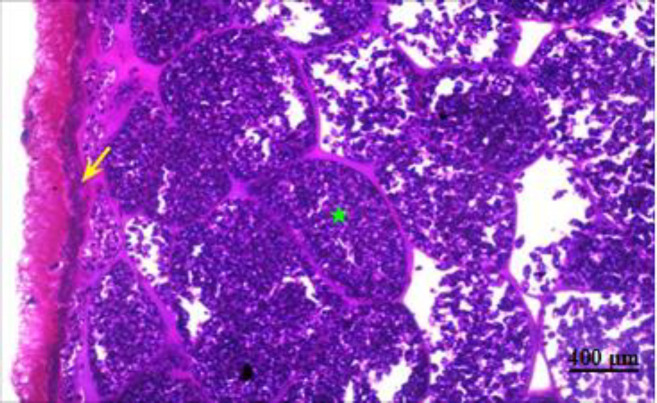

Results: By visual inspection, the overall prevalence of suspected sarcocystosis was 26.5%. The highest infection rate was detected visually from the esophagus followed by skeletal muscles and diaphragm whereas the least was recorded in the tongue. Histological and TEM examination showed that the cysts were packed with bradyzoites separated by multiple septa. 100% of the sarcocysts diagnosed visually in the esophagus and muscles were confirmed by PCR, compared to only 25% of those detected in the tongue.